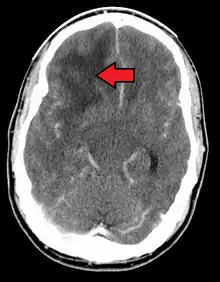

- اختبارات التصوير: وغالبًا ما يستخدم التصوير بالرنين المغناطيسي للمساعدة في تشخيص أورام الدماغ. في بعض الحالات، قد يتم حقن صبغة (مواد تباين) خلال وريد في ذراع المريض أثناء دراسة التصوير بالرنين المغناطيسي للمساعدة في إظهار الاختلافات في أنسجة الدماغ.

ويمكن أن تشمل الاختبارات، التصوير المقطعي المحوسب والتصوير المقطعي بالإصدار البوزيتروني.